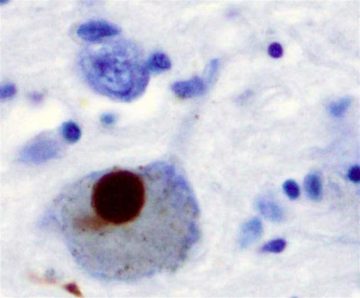

El doctor Dunckley es investigador en el recién formado Centro de Investigación de Enfermedades Neurodegenerativas, una asociación única entre la Universidad del Estado de Arizona (ASU, por sus siglas en inglés), y Banner Health. Las neuronas localizadas en una región del cerebro conocida como la sustancia negra son el objetivo principal para la enfermedad de Parkinson. Algunas de ellas producen dopamina, que disminuye a medida que la enfermedad avanza, causando deterioro en el movimiento normal.

Neuroinflamación, estrés oxidativo, disfunción mitocondrial y empalme alternativo anormal también se han implicado en la trayectoria de la enfermedad de Parkinson, aunque las causas exactas de la patología –que implica el deterioro de las neuronas dopaminérgicas en el cerebro medio acompañadas por altas tasas de demencia_ permanecen sin esclarecer.